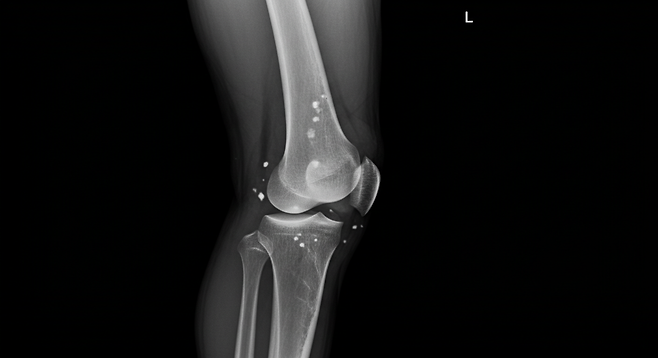

5. 관절 통증이 있을 때

관절에 통증이 생기면 무리하게 움직이지 말고,

- 적당히 쉬고,

- 찜질(온찜질)이나 스트레칭으로 통증을 완화하세요.

- 증상이 지속되면 전문의 상담을 받으시기 바랍니다.